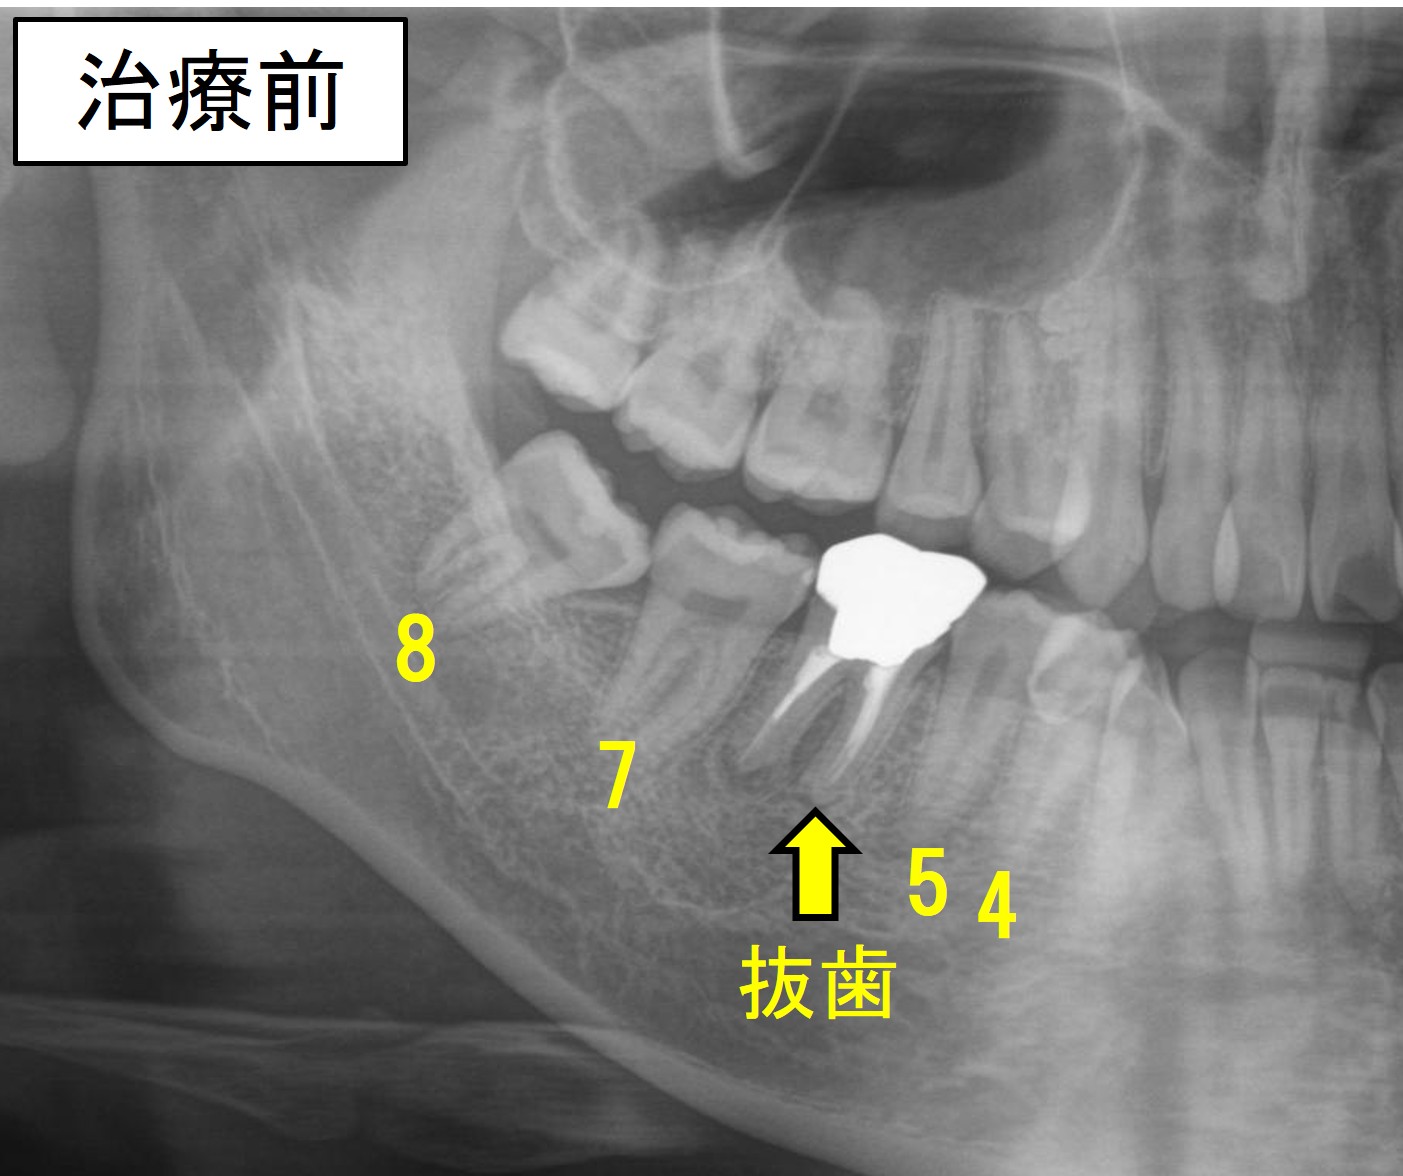

◆【症例8】パターン③ 親知らず(8番)により歯根吸収していた7番を抜いて、8番を利用したケース

次は、親知らず(8番)により、7番の歯根が大きく吸収していたため、状態の悪い7番を抜歯して、8番を矯正的に利用した症例をご紹介します。

後述しますが、CTを用いて診断しないと7番の歯根吸収の状態に気が付かない場合もあります。

7番を抜歯すると、8番は自然と生えてくることが多いです。

ただし、多くの場合は、手前に傾斜しながら生えてきますので、やはり矯正治療で傾斜を改善しながら、手前に動かす必要があります。

- 抜歯部位:上顎左右4番、下顎左右7番